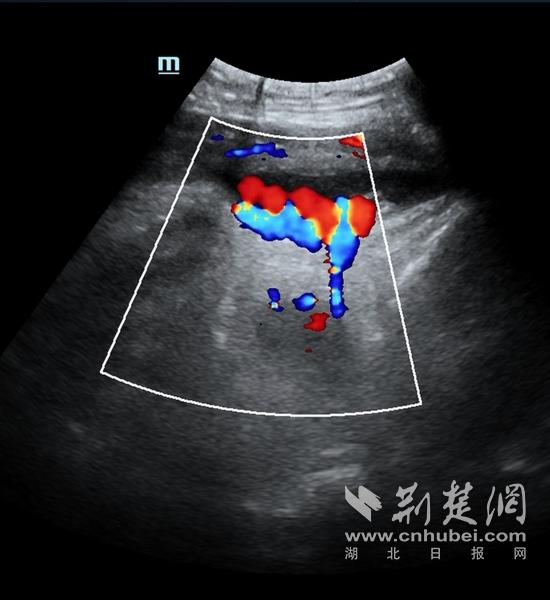

胎心监护显示胎儿心率曲线波动微弱,超声提示脐带绕颈已增至三周。宋晓晖主任判断可能存在胎儿窘迫,需立即手术。“当时我还想回家收拾待产包,宋主任说不能再等,每一分钟都可能发生意外。”崔女士回忆。

超声提示有脐带绕颈。摄影 张祖国